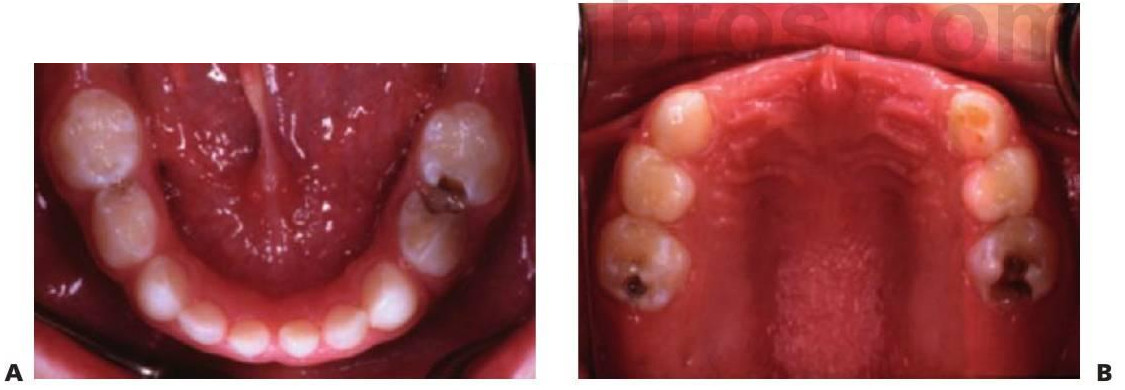

- Una fractura del reborde marginal en un diente temporal sugiere la afectación pulpar cariosa en contacto con una caries puntual (fig. 6.4A).

- La fractura de los rebordes triangulares oclusales o la socavación cariosa de las cúspides en las caries de fosas y fisuras también sugiere afectación cariosa (fig. 6.4B).

Por desgracia, el aspecto externo de la lesión cariosa puede llevar a confusión en algunos casos (fig. 6.5). Los síntomas persistentes que aparecen poco después de colocar una restauración indican afectación pulpar y la falta de sellado coronal desembocará también, inevitablemente, en una lesión pulpar. El examen radiográfico se revela esencial para complementar los hallazgos clínicos y aumentar la exactitud del diagnóstico.